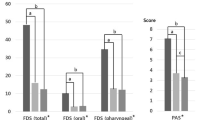

Table 2 presents the differences of swallowing function, including each component of the VDS, VDS total score, and FOIS between the TRACH and NO-TRACH groups. Among the components of the VDS, bolus formation and mastication were significantly more deteriorated in the TRACH group than in the NO-TRACH group. There was no significant difference in the total VDS score between the TRACH (35.17 ± 15.30) and NO-TRACH groups (29.25 ± 16.66, p = 0.247). FOIS was significantly lower in the TRACH group (2.33 ± 1.40) than that in the NO-TRACH group (4.33 ± 1.79, p = 0.001).

Table 3 shows the differences of swallowing kinematics between stroke patients with and without tracheostomies. The TRACH group showed significantly lower maximum vertical displacement (15.23 ± 7.39 mm, p = 0.011) and velocity (54.99 ± 29.59 mm/s, p = 0.011), and two-dimensional velocity (61.07 ± 24.89 mm/s, p = 0.013) of the larynx than the NO-TRACH group (20.18 ± 5.70 mm, 82.23 ± 37.30 mm/s, and 84.40 ± 36.05 mm/s, respectively). Maximum horizontal velocity (36.77 mm/s ± 16.97) of the hyoid bone was also significantly lower than NO-TRACH group (47.49 ± 15.73 mm/s, p = 0.032). However, there was no significant difference in the maximum angle of epiglottic tilt between two groups.